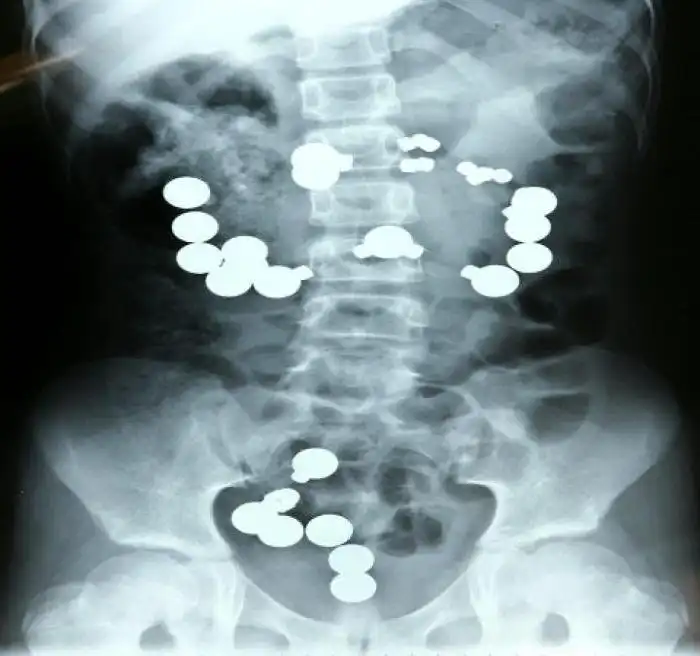

Необычные предметы в теле людей на рентгеновских снимках

На рентгеновских снимках людей порой можно обнаружить самые необычные предметы, которые находятся в их теле.